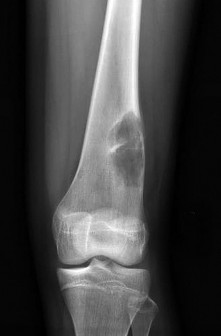

Question 32

An 8-year-old, 35 kg boy sustains a transverse midshaft fracture of the right femur. He is treated with titanium elastic nails (TENs). What is the most common complication associated with this surgical treatment?